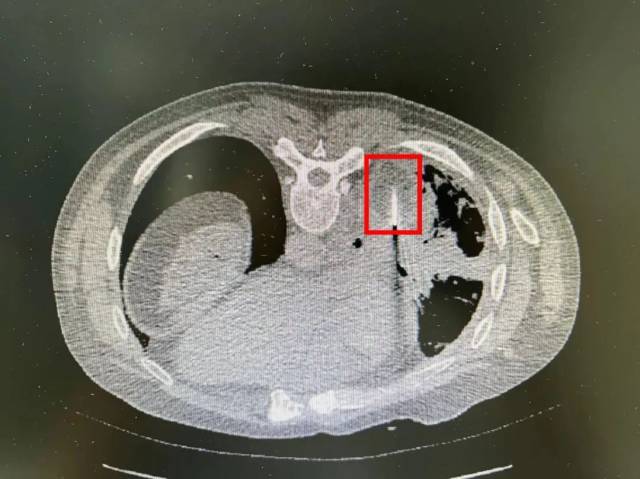

手术在CT室进行,呼吸二科陈绍森主任带领团队将氩氦刀冷冻消融针通过胸部肋间隙精准插入,经CT扫描确认氩氦刀进入肺癌肿瘤病灶内后,启动氩氦刀冻融系统开始冷冻治疗。整个手术过程历时1小时,陈叔没有感觉到任何不适,术后感觉良好,饮食、生活正常,无出现任何并发症。

术中冷冻消融冰球形成